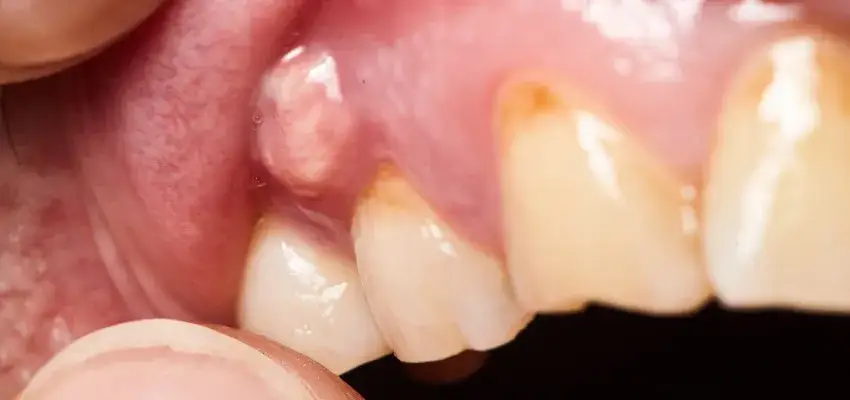

- Widoczna przetoka ropna na dziąśle, z której może wyciekać ropa, przynosząc chwilową ulgę.

Zmiany na dziąśle, na które musisz zwrócić uwagę

Na początku możesz zauważyć delikatny obrzęk dziąsła w okolicy chorego zęba. Dziąsło staje się zaczerwienione, tkliwe na dotyk i bolesne. To pierwszy widoczny znak, że w tkankach rozwija się stan zapalny. Nie lekceważ nawet niewielkiej opuchlizny, ponieważ szybko może się ona rozprzestrzenić.

Widoczne znaki: opuchlizna policzka, dziąsła i przetoka ropna

W zaawansowanym stadium ropnia obrzęk może być bardzo rozległy. Często obejmuje policzek, wargę, a nawet okolice oka lub obszar pod żuchwą. Twarz staje się asymetryczna, a skóra napięta i błyszcząca. Charakterystycznym objawem jest również pojawienie się przetoki ropnej to niewielki pęcherzyk lub uwypuklenie na dziąśle, z którego może wyciekać ropa. Chociaż wyciek ropy często przynosi chwilową ulgę w bólu, nie oznacza to, że problem zniknął. Wręcz przeciwnie, przetoka świadczy o tym, że infekcja znalazła ujście, ale jej źródło nadal jest aktywne.